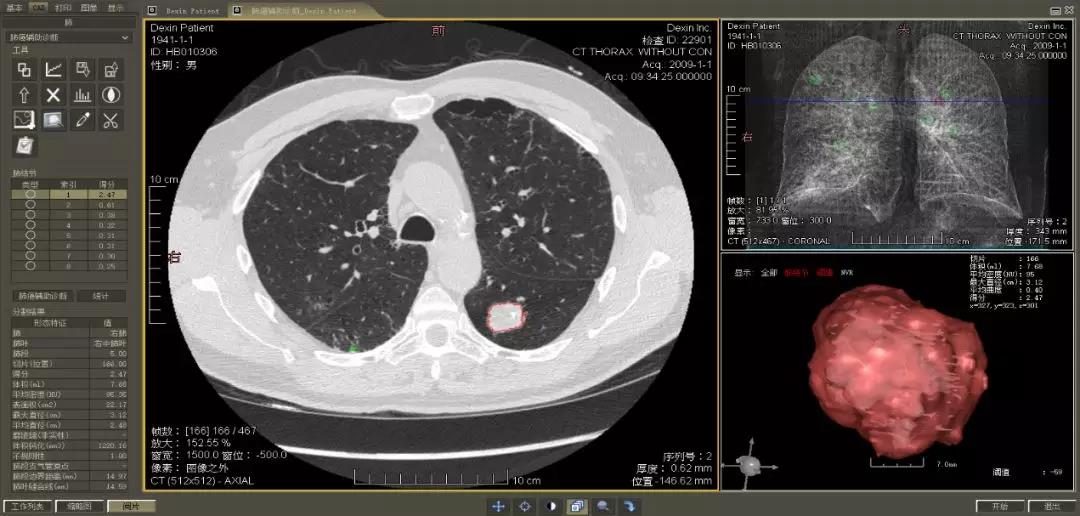

▲ 數(shù)字肺產(chǎn)品肺癌計算機輔助診斷

醫(yī)療影像智能分析是指運用人工智能技術、計算機視覺技術以及計算幾何技術對醫(yī)療影像進行自動分析,幫助醫(yī)生定位病癥、分析、跟蹤病情,并通過量化數(shù)據(jù)輔助醫(yī)生做出診斷,目前其旗艦產(chǎn)品“數(shù)字肺”已經(jīng)覆蓋多種肺部疾病的早期檢測、診斷、跟蹤、術前規(guī)劃等完整的醫(yī)療流程。在臨床實踐中,超過80%的醫(yī)療數(shù)據(jù)來自醫(yī)療影像,這些影像數(shù)據(jù)通常需要專業(yè)醫(yī)生進行解讀,工作的重復性高、效率偏低。如果能夠運用智能影像分析技術,同時結合臨床表現(xiàn)以及既往病例進行全面分析,那么就可以大幅度提升影像診斷效率和準確性,讓專業(yè)醫(yī)生的寶貴時間集中在復雜病情的診斷和治療等環(huán)節(jié)。